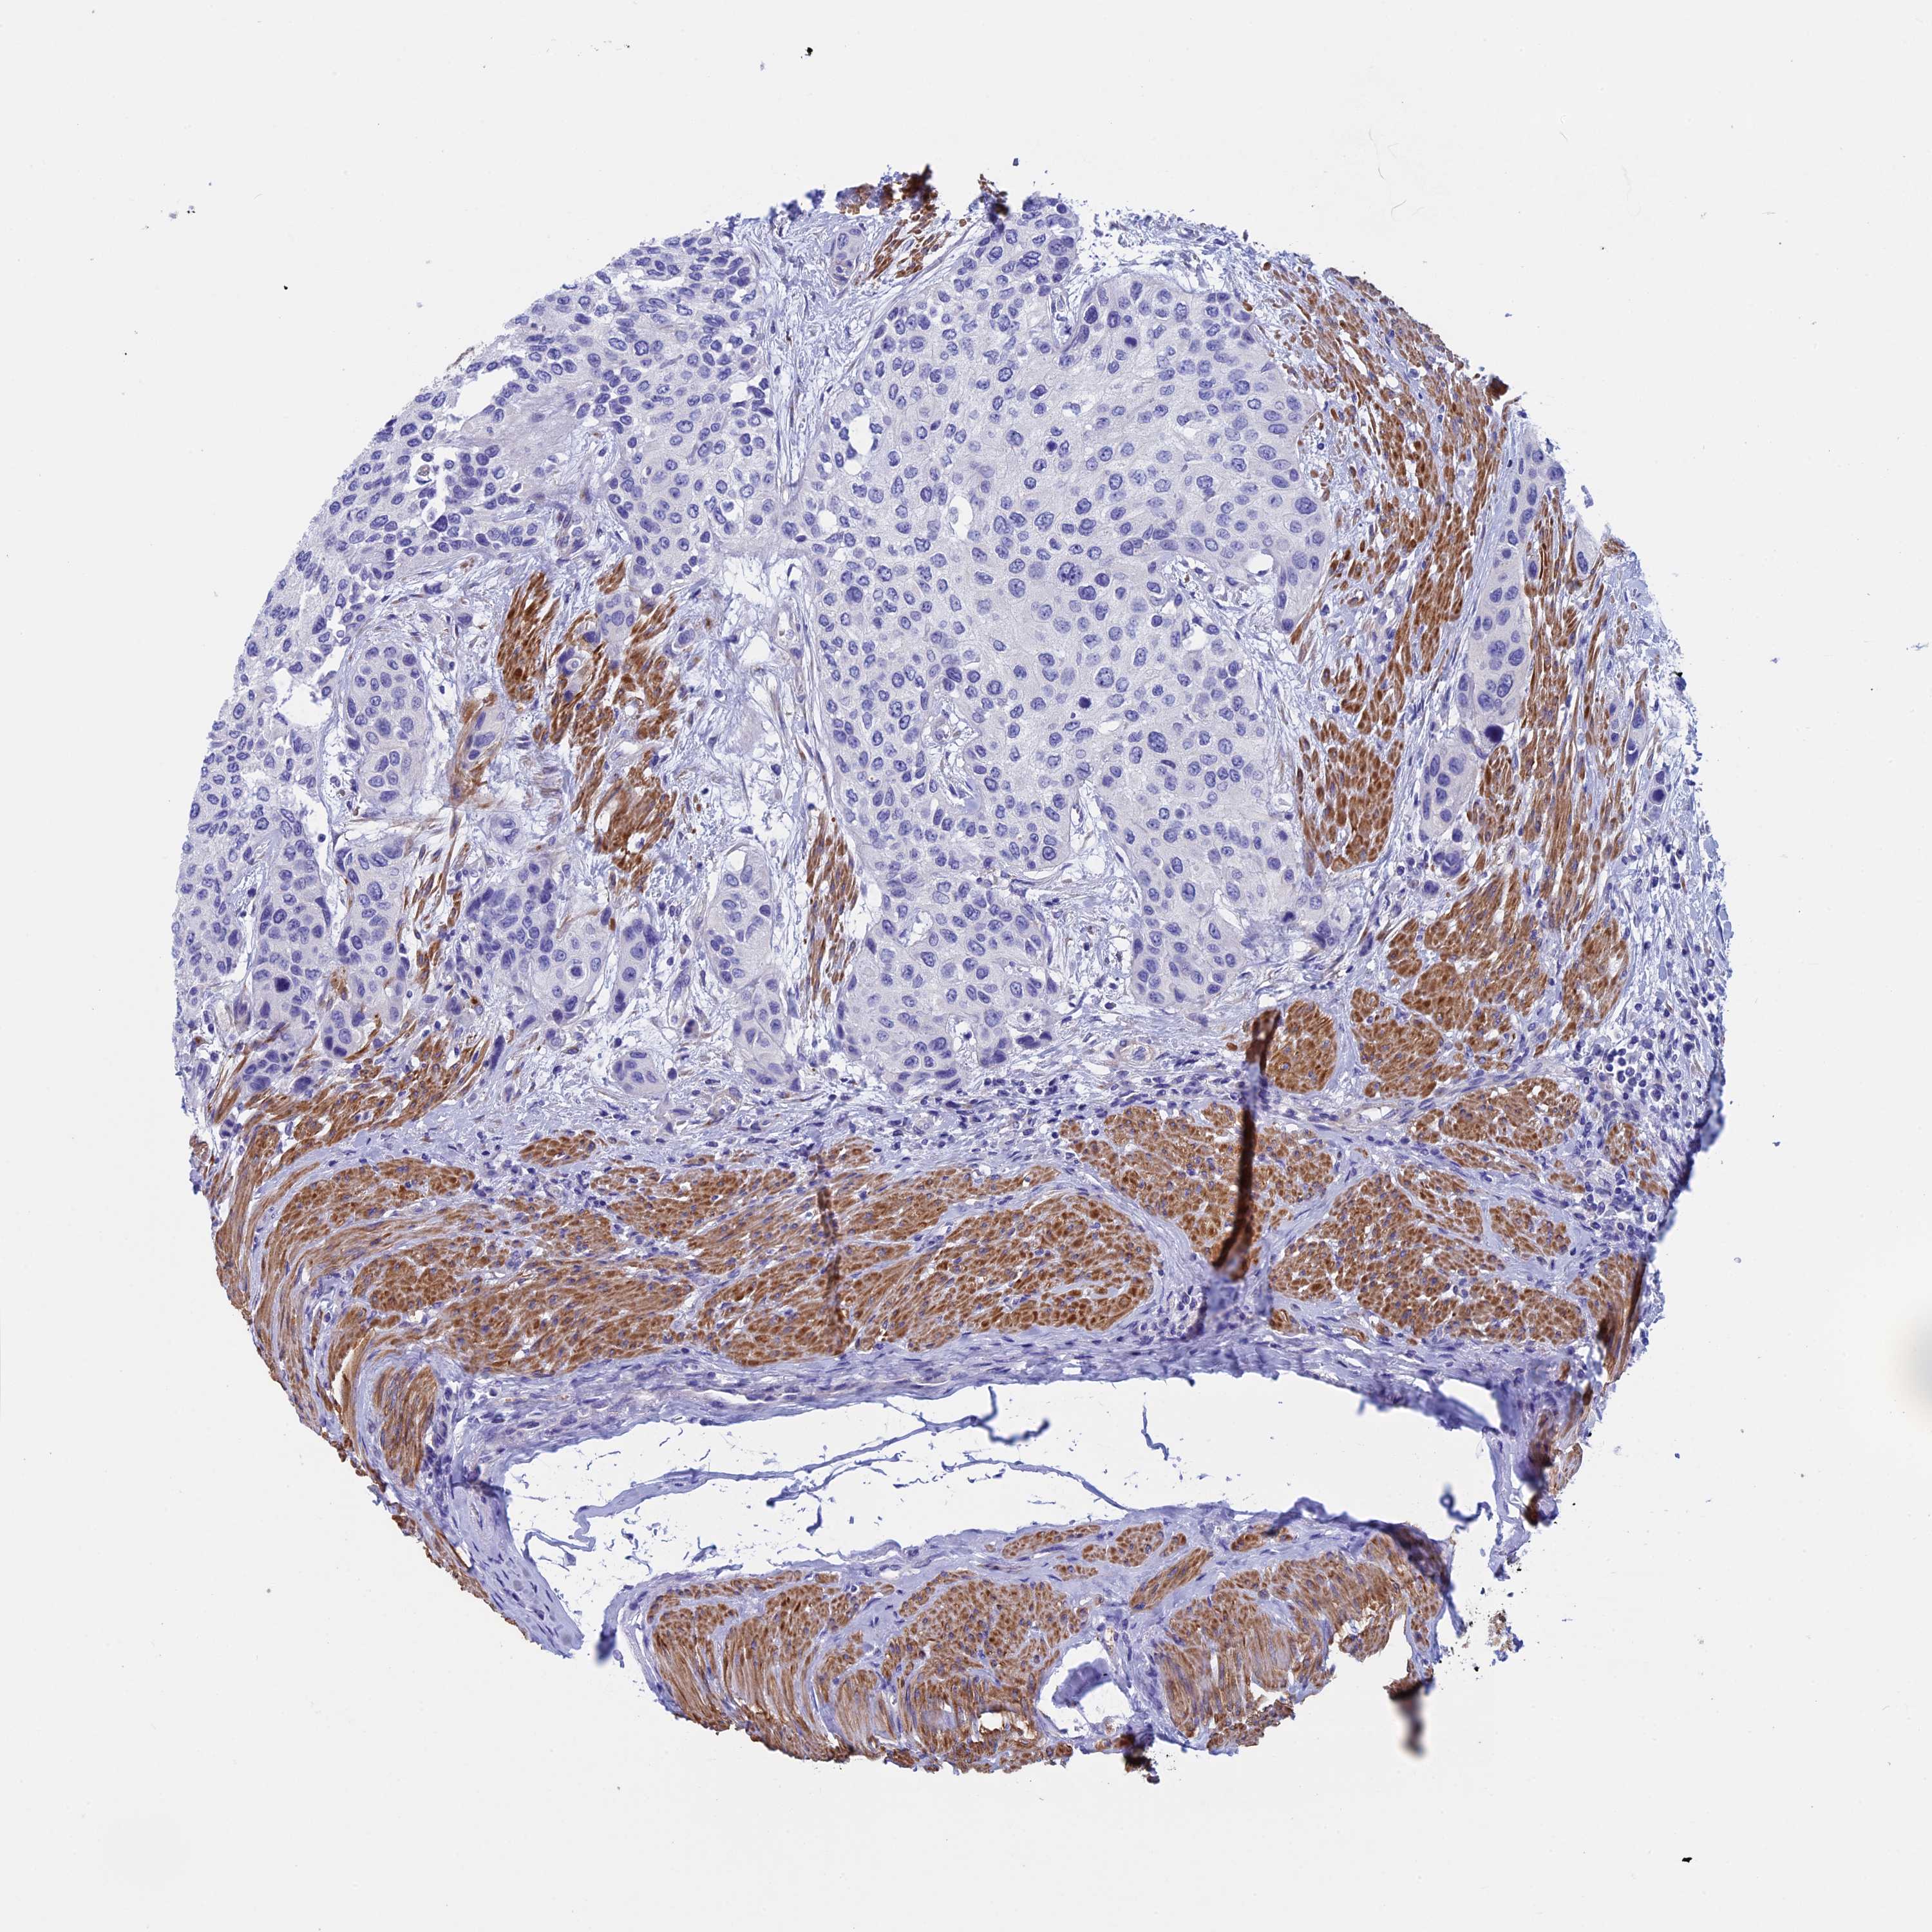

UROTHELIAL CANCER - Protein expressioni

A mouse-over function shows sample information and annotation data. Click on an image to view it in a full screen mode. Samples can be filtered based on level of antibody staining by selecting one or several of the following categories: high, medium, low and not detected. The assay and annotation is described here.

Antibody stainingi

Antibody staining in the annotated cell types in the current human tissue is reported as not detected, low, medium, or high, based on conventional immunohistochemistry profiling in selected tissues. This score is based on the combination of the staining intensity and fraction of stained cells.

Each image is clickable and will lead to virtual microscopy that enables deeper exploration of all samples and also displays staining intensity scores, fraction scores and subcellular localization as well as patient and tissue information for each sample.

Antibody HPA039695

Staining

High

Medium

Low

Not detected

Intensity

Strong

Moderate

Weak

Negative

Quantity

>75%

75%-25%

<25%

None

Location

Nuclear

Cytoplasmic/membranous

Cytoplasmic/membranous,nuclear

Urothelial carcinoma, High grade

Urothelial carcinoma, Low grade